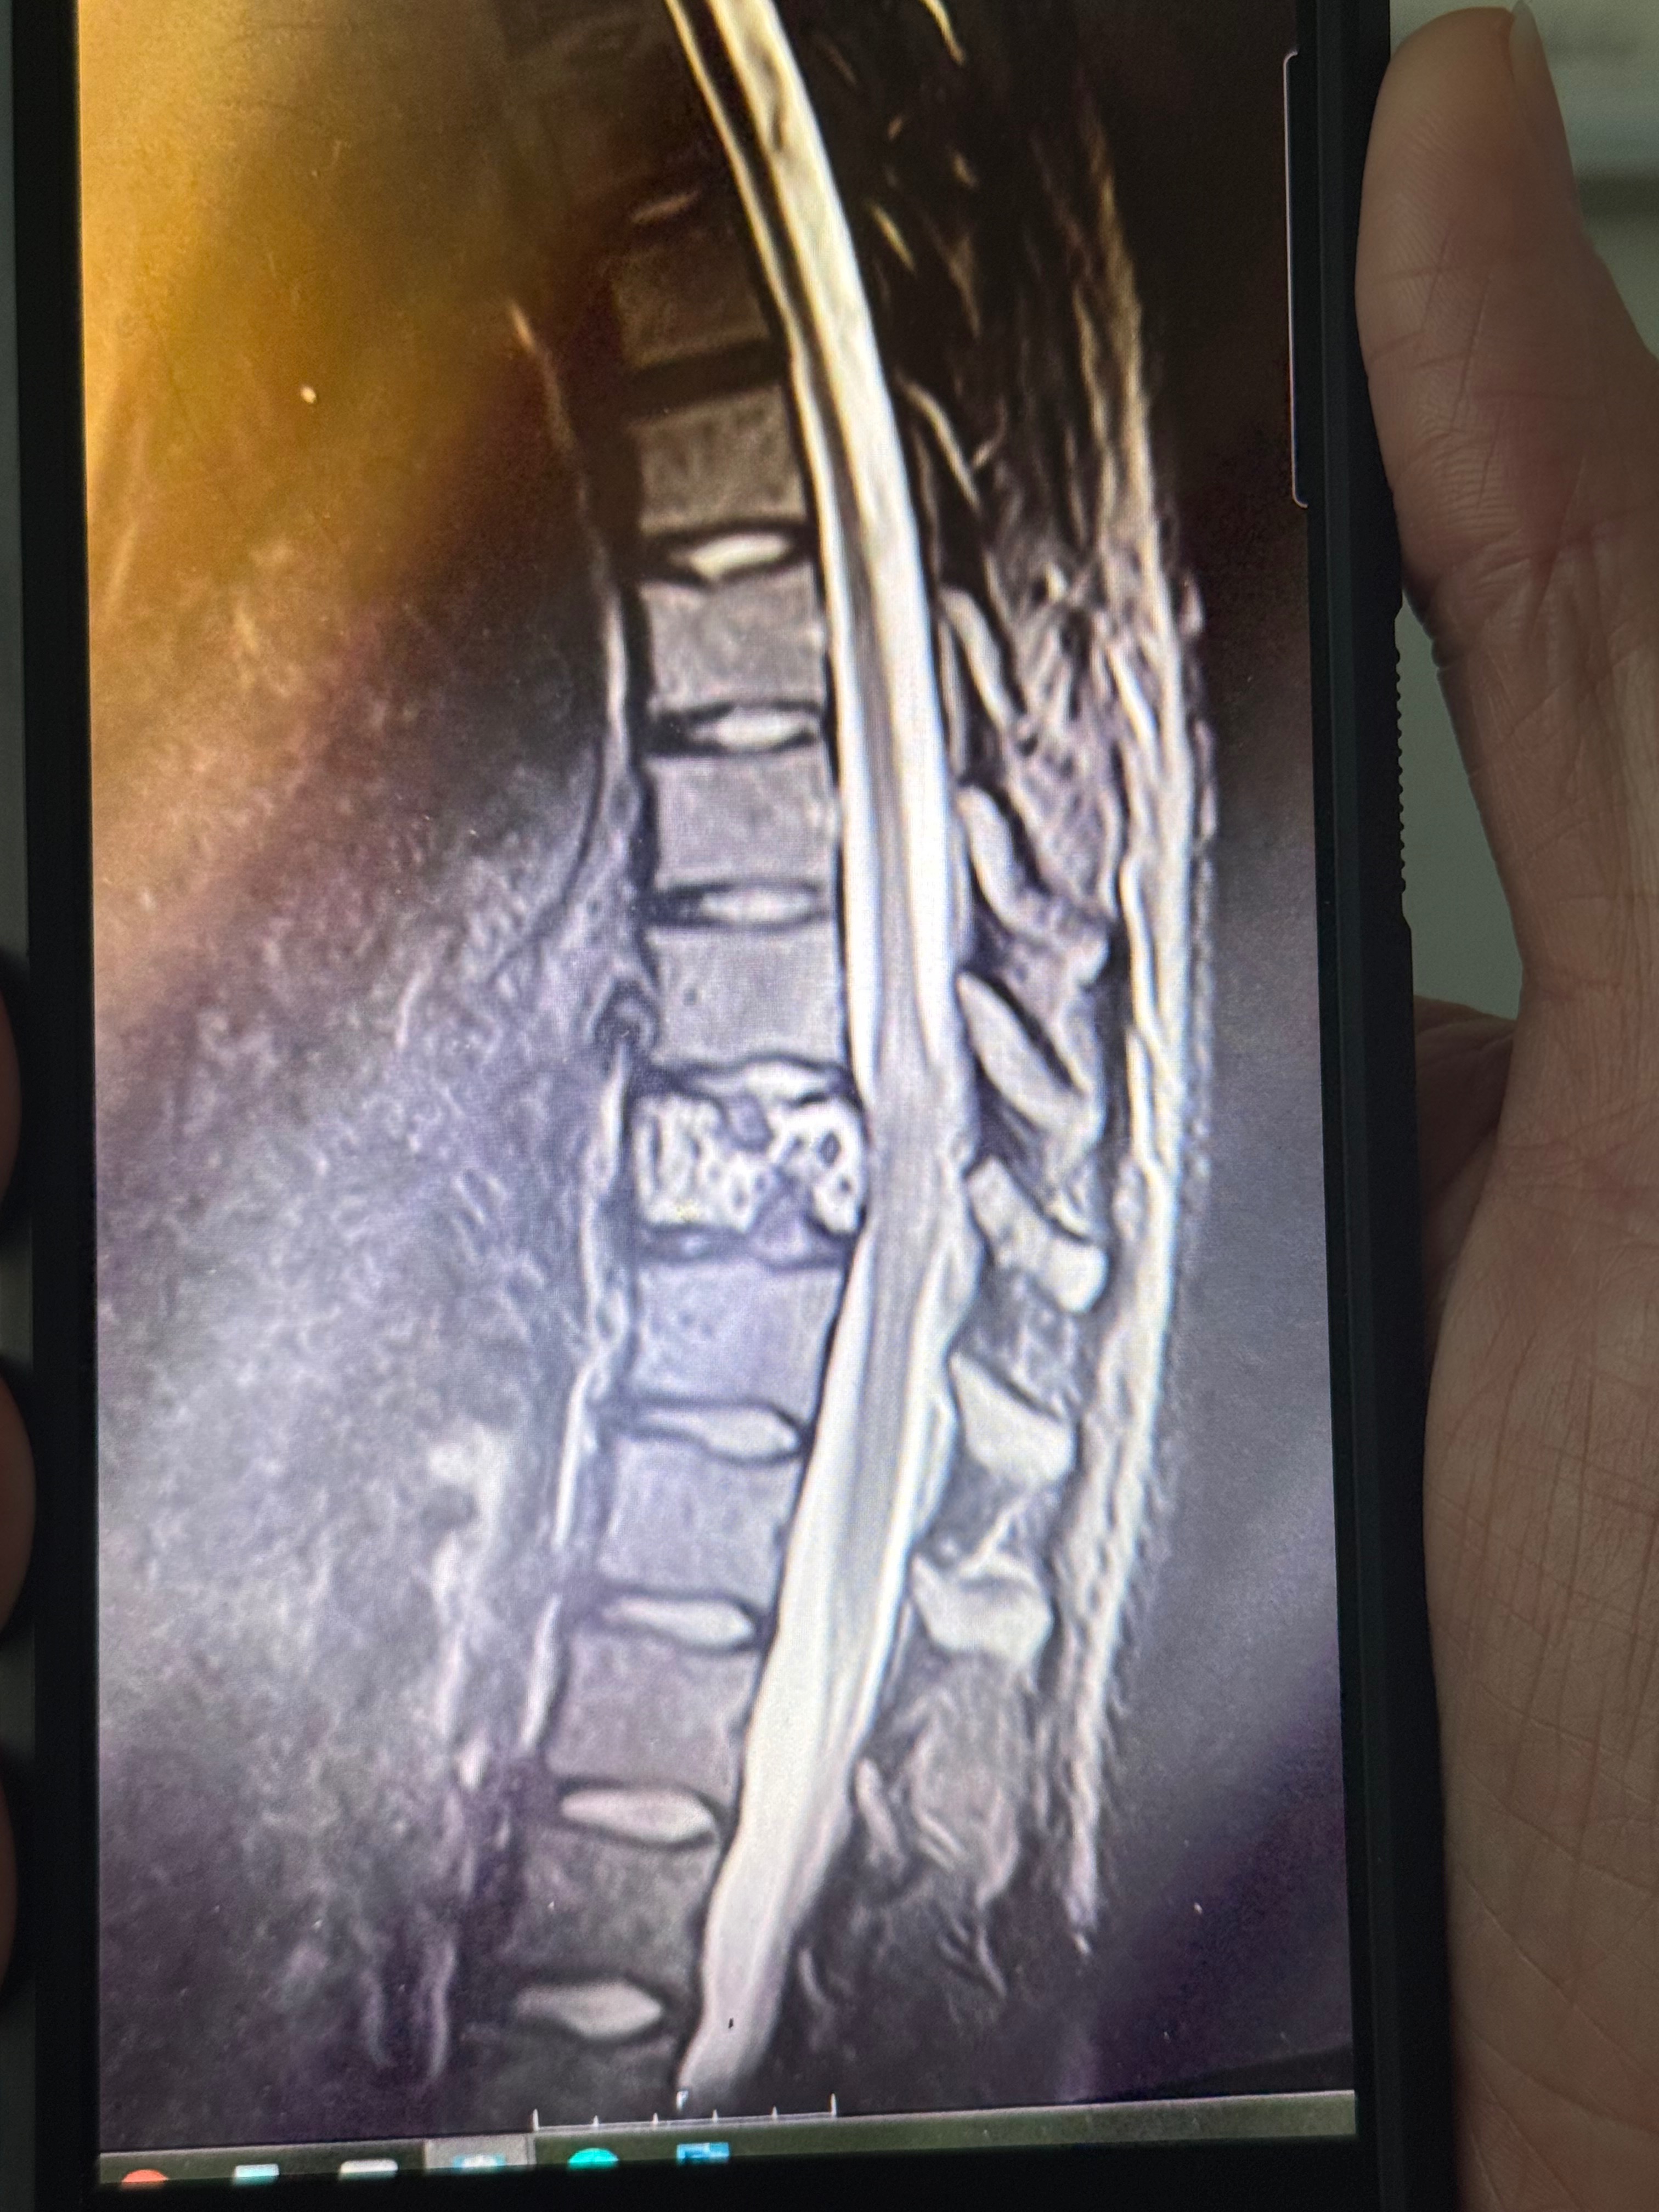

Iliana has now been seen by the surgeon and here are the current updates. The bone (t10 located in her spine) seen in the MRI, is being replaced (think a termite in wood) by an unknown mass. They cannot remove the affected area due do the risk of bleeding out or organ failure in surgery. The best they can do is remove and vertebrae to release pressure on the spinal cord, put supportive bolts above and below the fragile disk and complete a biopsy on the mass. The question is, “what is the mass?” the surgeon bluntly explained how its either bone cancer or some sort of infection in the affected bone. We will not the result of the biopsy until 10-14 days after the surgery (7:30AM march 14 PST). Recovery will be a journey that will last months and when the diagnosis comes that journey will change and may be prolonged. We humbly ask for prayers that it is not cancer, a safe and efficient surgery, and a painless (as possible) recovery. Iliana is so grateful for the prayers and financial help in these uneasy, scary, times. God bless.

My best friend Iliana is facing one of the most challenging moments of her life. After months of unexplained symptoms and not being heard by doctors, she was finally diagnosed with a mass in her spine that is compressing her spinal cord. This has caused her significant difficulty walking and numbness throughout the lower half of her body. The situation has become urgent, and she now needs to undergo a very invasive, emergency surgery to relieve the pressure and prevent further damage.